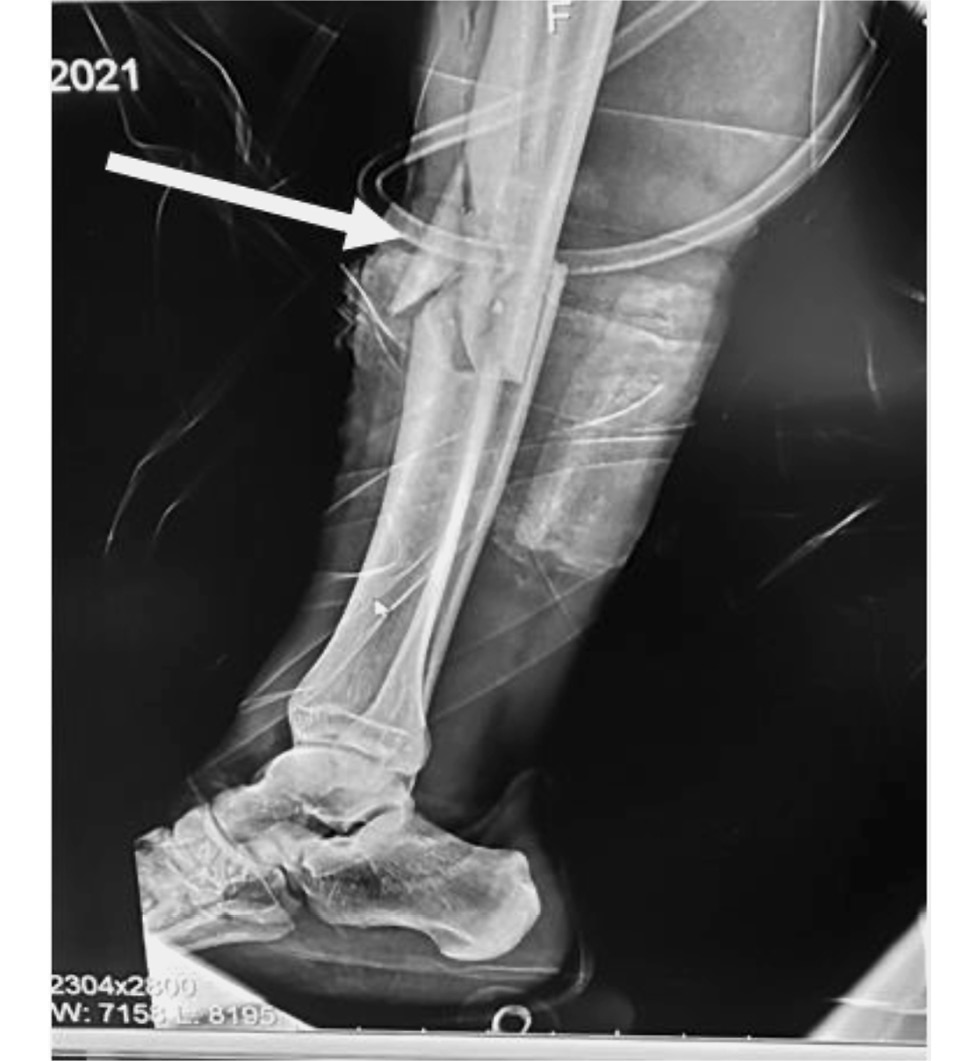

Переломы костей голени при падении имели место в 33 случаях, при этом большеберцовая кость страдала наиболее часто (n=28). При падении у самокатчиков наблюдались переломы всех сегментов костей голени, однако переломы так называемого плато большеберцовой кости (рис. 3) наблюдались в половине случаев её переломов (n=14). Такие переломы были закрытыми, оскольчатыми (или многооскольчатыми), вдавленными, локализовались на одном (наружном, внутреннем) либо обоих мыщелках кости, а наружные повреждения в их проекции отсутствовали.

Рис. 3. Компьютерная томография коленного сустава, выполненная пострадавшему после падения с электросамоката: а ― стрелками обозначена локализация многооскольчатого перелома мыщелка большеберцовой кости; b (3d-реконструкция) ― стрелками обозначена локализация оскольчатого перелома на уровне плато (мыщелка) большеберцовой кости.

При столкновениях электросамокатов и движущихся автомобилей (n=2) у обоих пострадавших формировались диафизарные переломы двух костей голени на одном уровне — средней трети. В одном из них в проекции перелома на передней поверхности голени имелась ушибленная рана. При изучении рентгенограмм костей голени в боковой проекции у 21-летнего пострадавшего, управлявшего электросамокатом, был обнаружен осколок большеберцовой кости, имеющий треугольную форму (так называемый треугольник Мессерера; рис. 4), который считается характерным признаком при столкновении движущихся автомобилей с пешеходами. При изучении характера переломов при падениях с самокатов таких особенностей не наблюдалось.

Рис. 4. Рентгенография костей правой голени (в боковой проекции) пострадавшего водителя электросамоката при столкновении с движущимся автомобилем. Стрелкой показан характерный отломок треугольной формы.